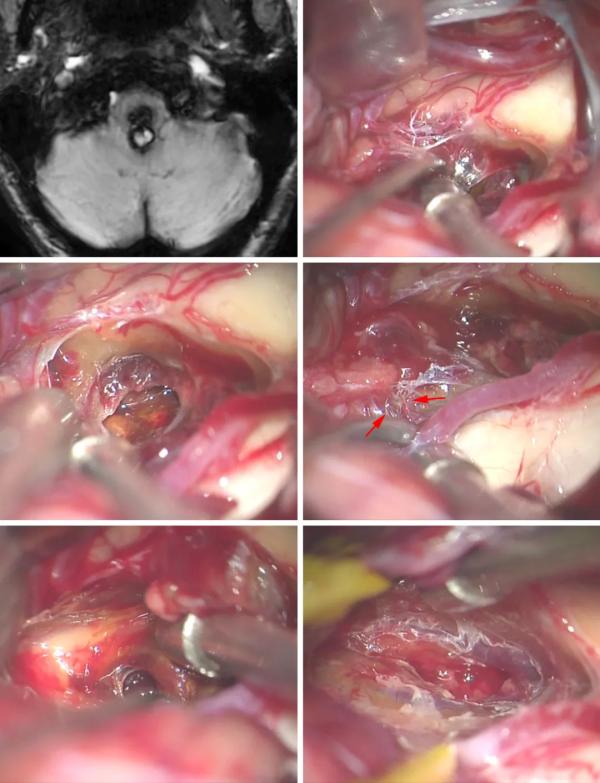

圖1:顯露CM后,用吸引器或垂體咬骨鉗清除CM內(nèi)與周圍的血腫(A)。然后游離小的供血?jiǎng)用},電凝并切斷(B)。推移減壓的病灶囊與膠質(zhì)邊緣分開(C )。仔細(xì)保護(hù)DVA,與病灶分開(D)。

圖2:這個(gè)橋腦后部的CM經(jīng)膜髓帆入路到達(dá),在四腦室底刺激描記面丘(上排的照片)。清除血腫可創(chuàng)造額外的空間;電凝并切斷供血?jiǎng)用}(中排)。然后將病灶囊從手術(shù)殘腔的膠質(zhì)壁上鈍性分離下來(lái)(黃色箭號(hào)),在切除結(jié)束時(shí)保留DVA(藍(lán)色箭號(hào))(下排)。

圖6:這個(gè)延髓后部的CM經(jīng)枕下開顱顯露,早期確認(rèn)了CM的終末供血血管(上排圖像)。CM內(nèi)的血腫已清除減壓,顯露起源于對(duì)側(cè)PICA的其他終末供血血管(中排,箭號(hào))。CM可有分隔(左下圖),因此需完全、謹(jǐn)慎地檢查手術(shù)殘腔,才能做到完全切除病灶(右下圖)。